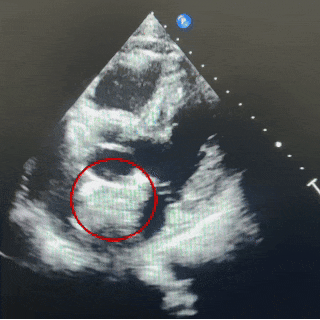

经食道超声描述:四腔心切面观:房间隔总长约48mm,中部卵圆窝处菲薄。房间隔中部回声中断约12.6mm,残端距二尖瓣环约23mm(软缘,房间隔中部菲薄),距房顶部约13mm(硬缘)。双腔切面观:房间隔中部回声中断约14.6mm,残端距上腔静脉约15.8mm(硬缘),距下腔静脉约23.8mm(硬缘)。大动脉短轴切面观:房间隔回声中断约12mm,主动脉侧几乎无残端,距心房侧约18mm(硬缘)。CDFI: 房水平可见左向右分流血流信号。三尖瓣口见少量反流血流信号。

超声提示:继发孔型房间隔缺损,房水平左向右分流。

超声四腔心切面下可见封堵器双盘骑跨在房间隔两侧

四腔心切面